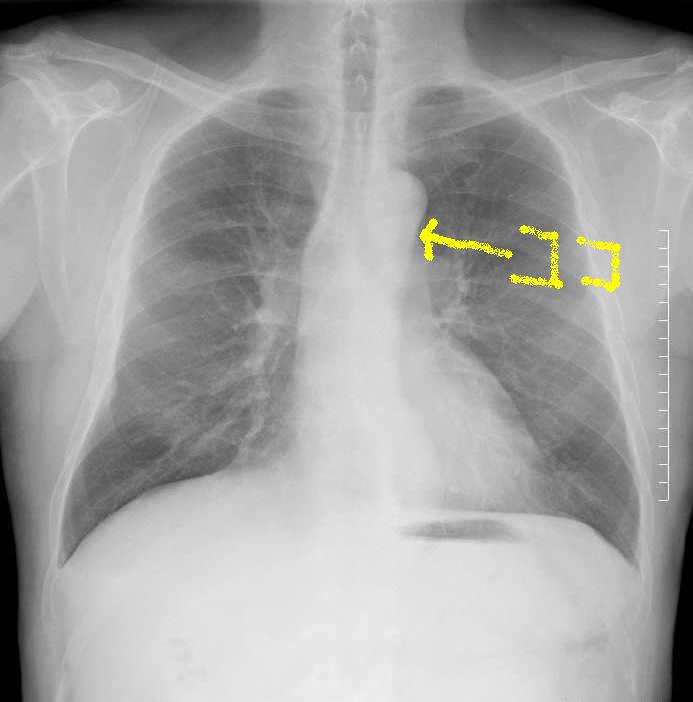

B正面像で見えるリンパ節

傍気管線、A-P window、気管分岐部は必ずチェックしましょう。

C縦隔や横隔膜の動きを見る

縦隔の所見

縦隔を見るときに、ボーッと見ていては所見を見逃します。

各種の線を追いかけていきましょう。

こちらを見て下さい。